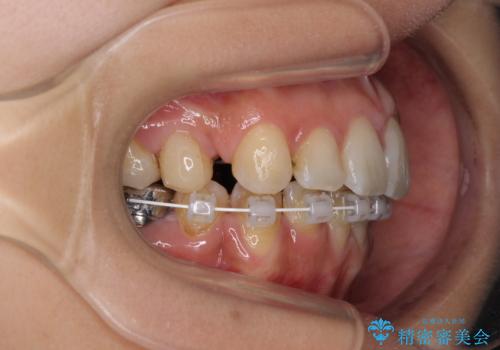

デコボコと口元の突出感 ハーフリンガルでの抜歯矯正

- 矯正装置

- ハーフリンガル

- 前歯のデコボコと上顎の前突感による口の閉じにくさを気にして来院された患者様です。

目立たない装置を希望されたので、上顎が裏側装置のハーフリンガルを選択し、上下左右の小臼歯(計4歯)を抜歯して矯正治療を行うこととしました。